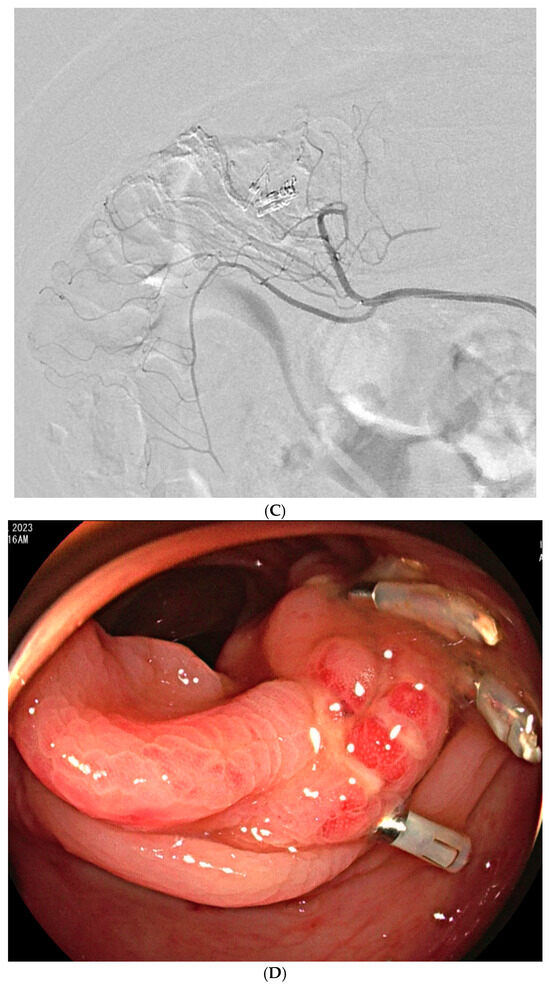

Embolization with Quick-Soluble Gelatin Sponge Particles for Lower Gastrointestinal Bleeding: A Multicenter Study

by Chang Ho Jeon, Seung Boo Yang, Woo Jin Yang, Ji Hoon Shin, Kyu-Pyo Kim, Jung-Hoon Park and Jin-Hyoung Kim

Medicina 2025, 61(11), 1964; https://doi.org/10.3390/medicina61111964 - 31 Oct 2025

Background and Objectives: Transarterial embolization (TAE) serves as a valuable alternative for gastrointestinal bleeding when endoscopy fails or is inaccessible. Quick-soluble gelatin sponge particles (QS-GSPs) dissolve rapidly and may reduce ischemic complications compared to permanent embolic agents. This study evaluated the safety and [...] Read more.

Background and Objectives: Transarterial embolization (TAE) serves as a valuable alternative for gastrointestinal bleeding when endoscopy fails or is inaccessible. Quick-soluble gelatin sponge particles (QS-GSPs) dissolve rapidly and may reduce ischemic complications compared to permanent embolic agents. This study evaluated the safety and effectiveness of TAE using QS-GSPs for acute lower gastrointestinal bleeding. Materials and Methods: This retrospective multicenter study analyzed patients who underwent TAE with QS-GSPs for acute nonvariceal lower GI bleeding between 2021 and 2024. Technical success (occlusion or stasis of blood flow in the target artery), clinical success (cessation of bleeding symptoms with hemodynamic stability during the week following TAE without major complications), and procedure-related complications were assessed. Results: A total of 29 patients (mean age 64.9 years) were included. Active bleeding was detected in 6 patients (20.7%) on angiography. Embolized arteries included jejunal (n = 7), ileal (n = 7), ileocolic anastomotic (n = 1), cecal (n = 2), colic (n = 7), and rectosigmoid (n = 5) arteries. QS-GSPs (150–350 μm (n = 10) or 350–560 μm (n = 19)), which dissolve completely within several hours, were used as the sole embolic agents. Technical and clinical success rates were 100% and 75.9% (22/29), respectively. Clinical failure occurred in seven patients (24.1%) due to persistent (n = 4) or recurrent (n = 3) bleeding within one week. Transient bowel ischemia occurred in two patients (6.9%) but resolved spontaneously. The clinical success rate did not differ significantly between patients with active bleeding (66.7%) versus those without (73.9%). Conclusions: TAE with QS-GSPs for acute lower GI bleeding demonstrated a favorable safety profile with clinical success exceeding 75%. Transient bowel ischemia occurred in 6.9% of patients with spontaneous resolution, and no bowel infarction was observed. Full article

Show Figures

Figure 1